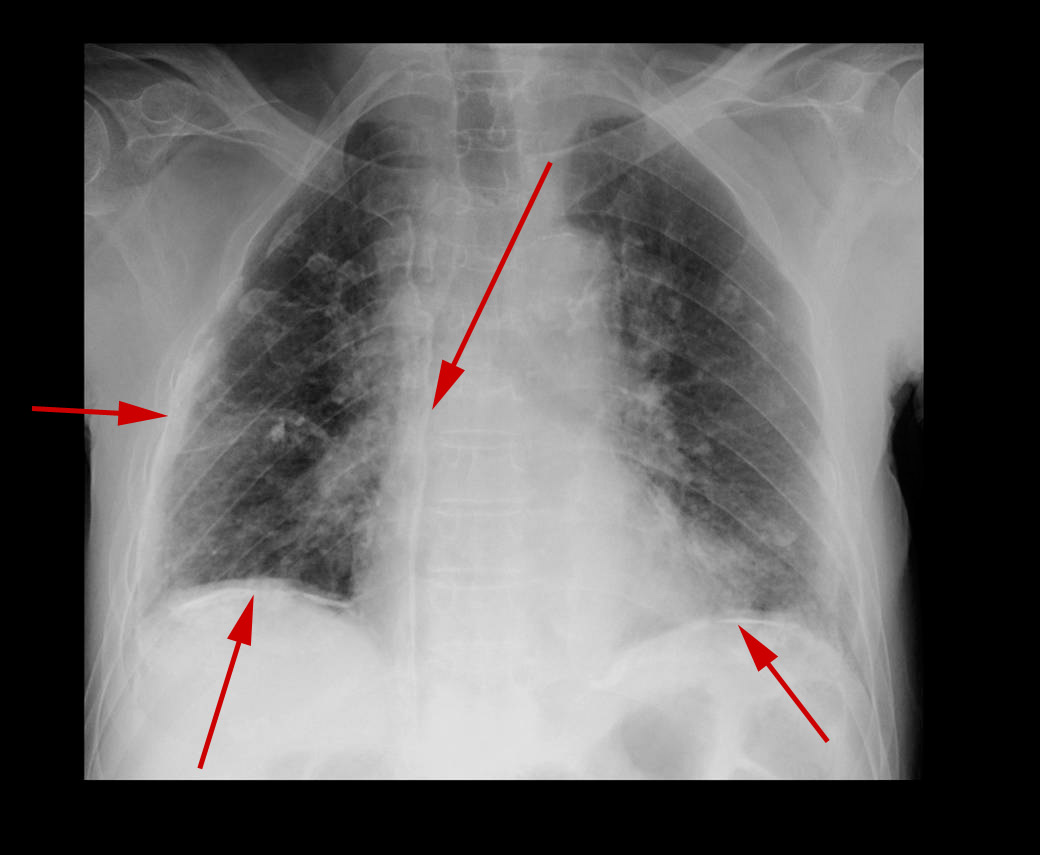

Patienten har for længe siden inhaleret asbest. Nu er der fremkommet forkalkninger (pile) i lungehinderne, som medvirker til at stivgøre lungerne.